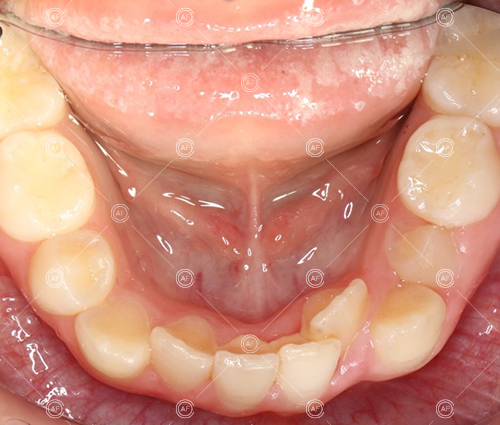

about this case…MH presented with class 1 incisors on the class 1 skeletal base with a slightly increased vertical proportion. She had severe crowding in the upper arch and moderate crowding in the lower. Due to the crowding in the lower arch, the lower centre line was off to the left by 2mm.

Buccal segments were essentially class 1 on the right hand side and a full unit class 2 on the left. This is due to buccal exclusion of the upper left 3 and mesial drift of the upper buccal segment.